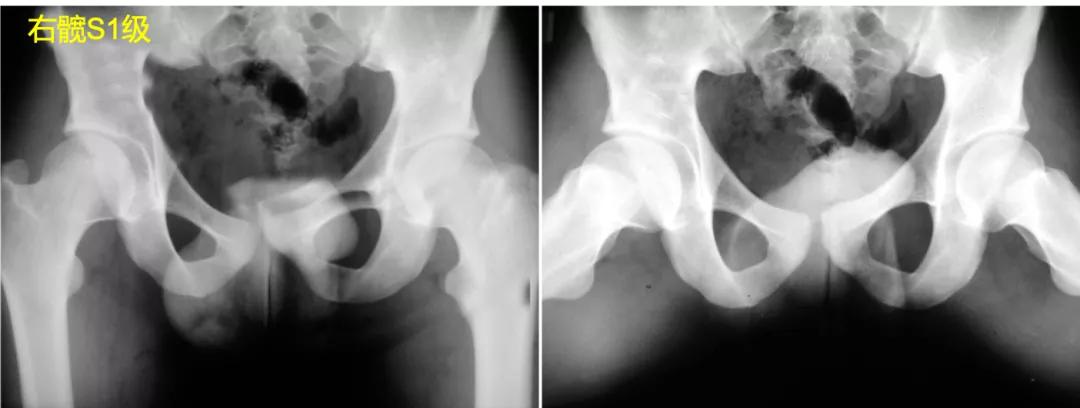

S1:影像学正常髋关节。

S2:股骨头呈圆形(不圆不超过2mm),在髋关节正侧位片中与髋臼呈同心状,但存在股骨头膨大、股骨颈变短。